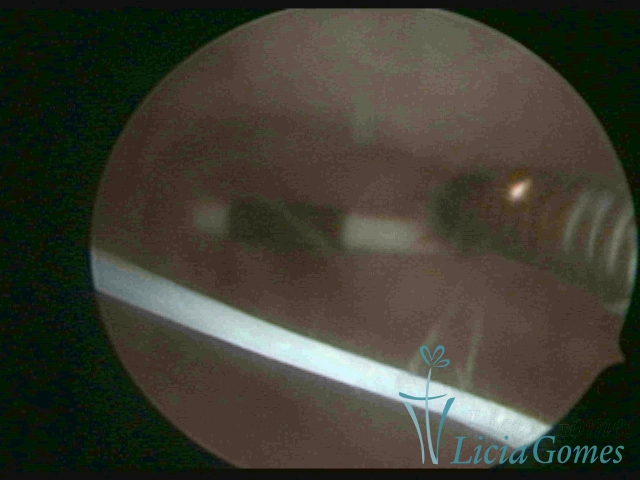

Extremidade distal do DIU

×